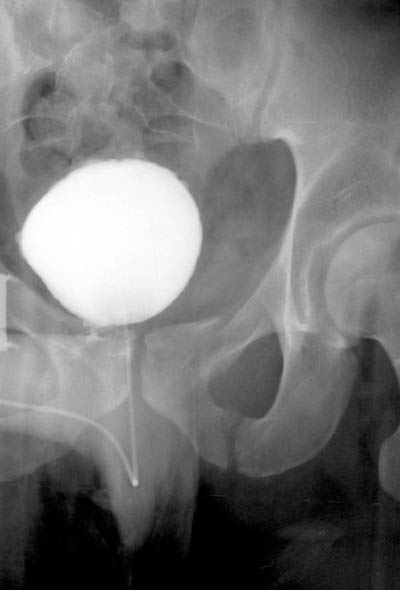

23) What abnormalities of the pelvis can be observed in the image below?

24) Based on your findings, name the condition shown in the image above.

25) Name the abnormality shown in the image below.